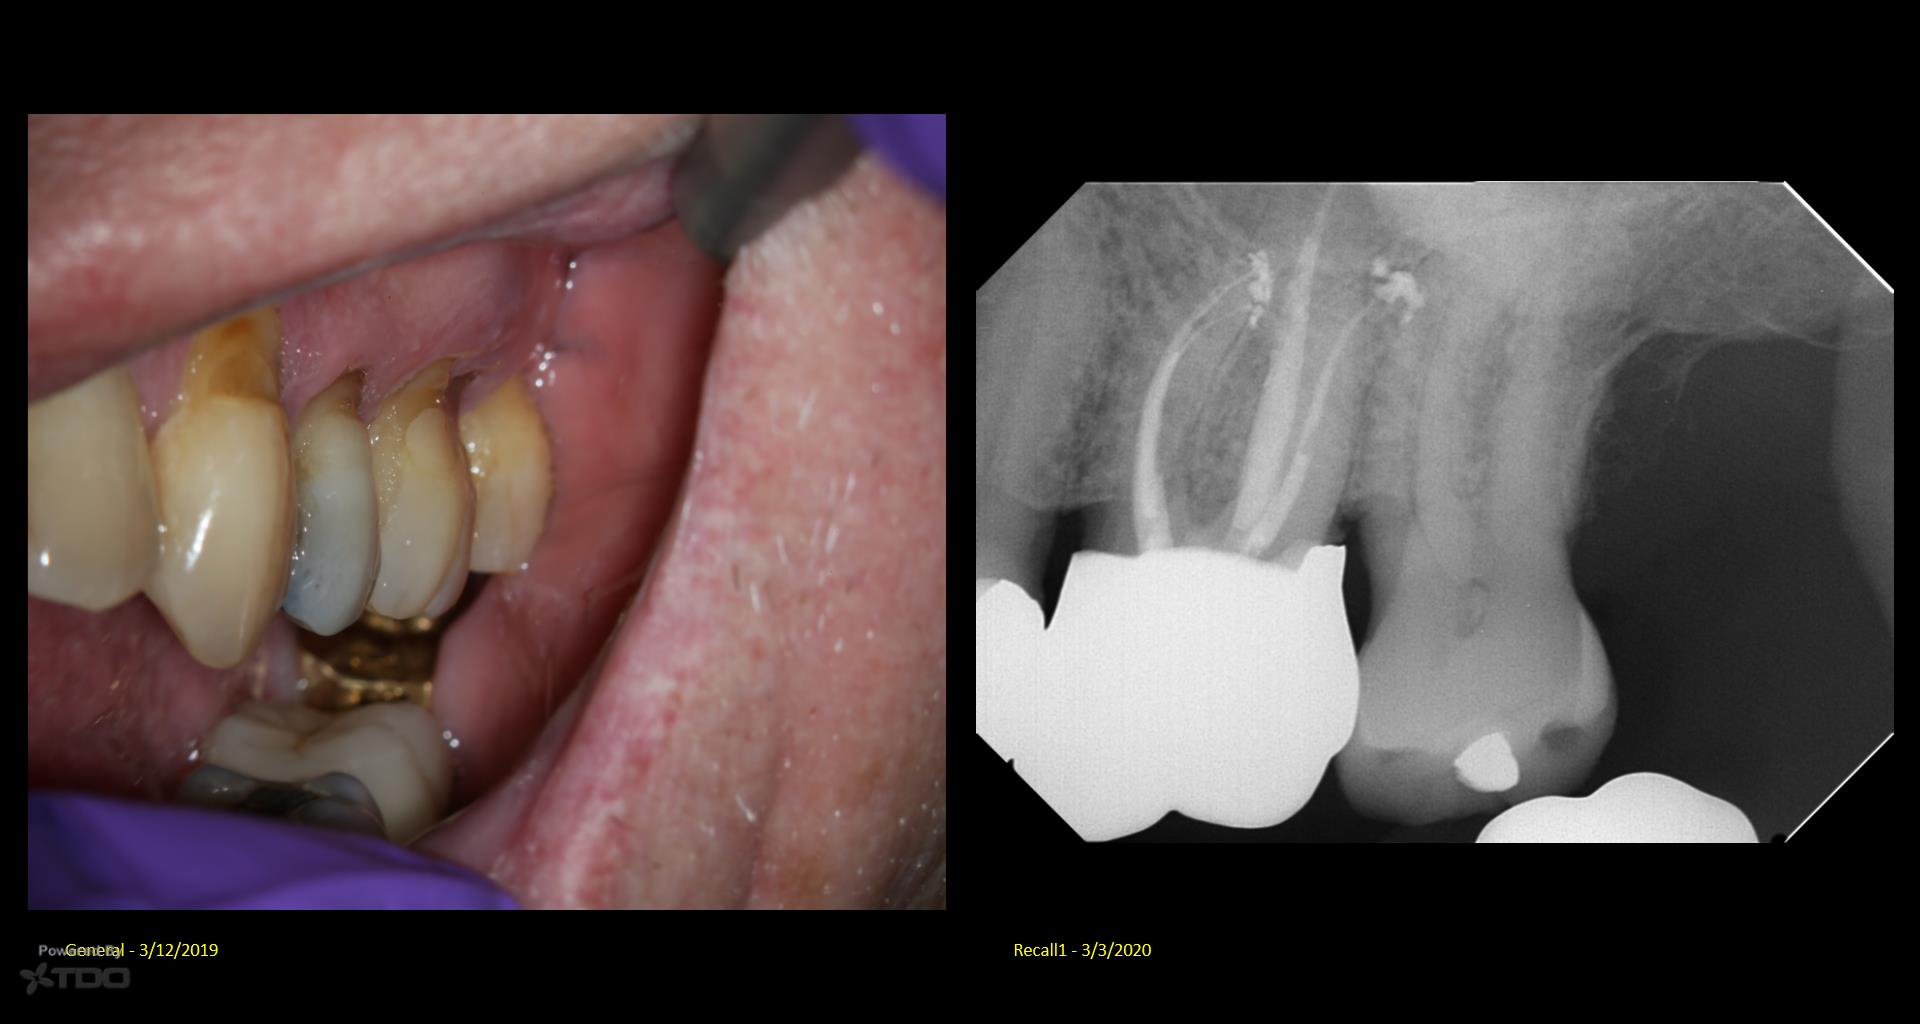

Fascinating read about the 1 year GW recall. The visual aid teeth cleaning image by doctor elevates the comprehension of the subject matter and makes the content more engaging. Fence Decking Supplier in Toms River NJ

Fascinating read about the 1 year GW recall. The visual aid teeth cleaning image by doctor elevates the comprehension of the subject matter and makes the content more engaging.